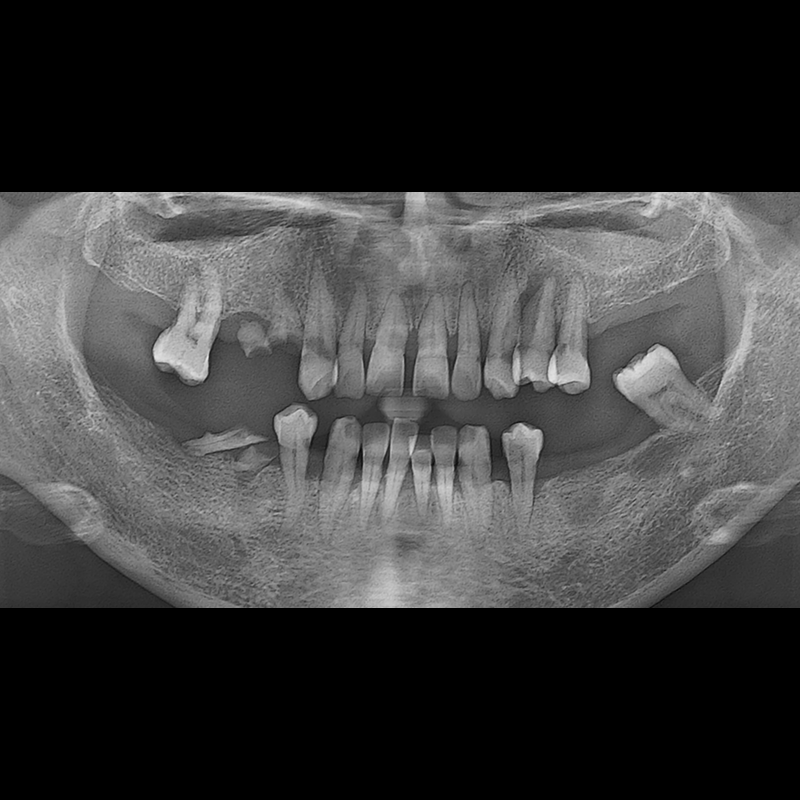

IMPLANT

BEFORE AFTER

种植牙前后的照片 2025.05.30

在缺失的牙齿部分和难以挽救的牙齿位置植入了种植牙。